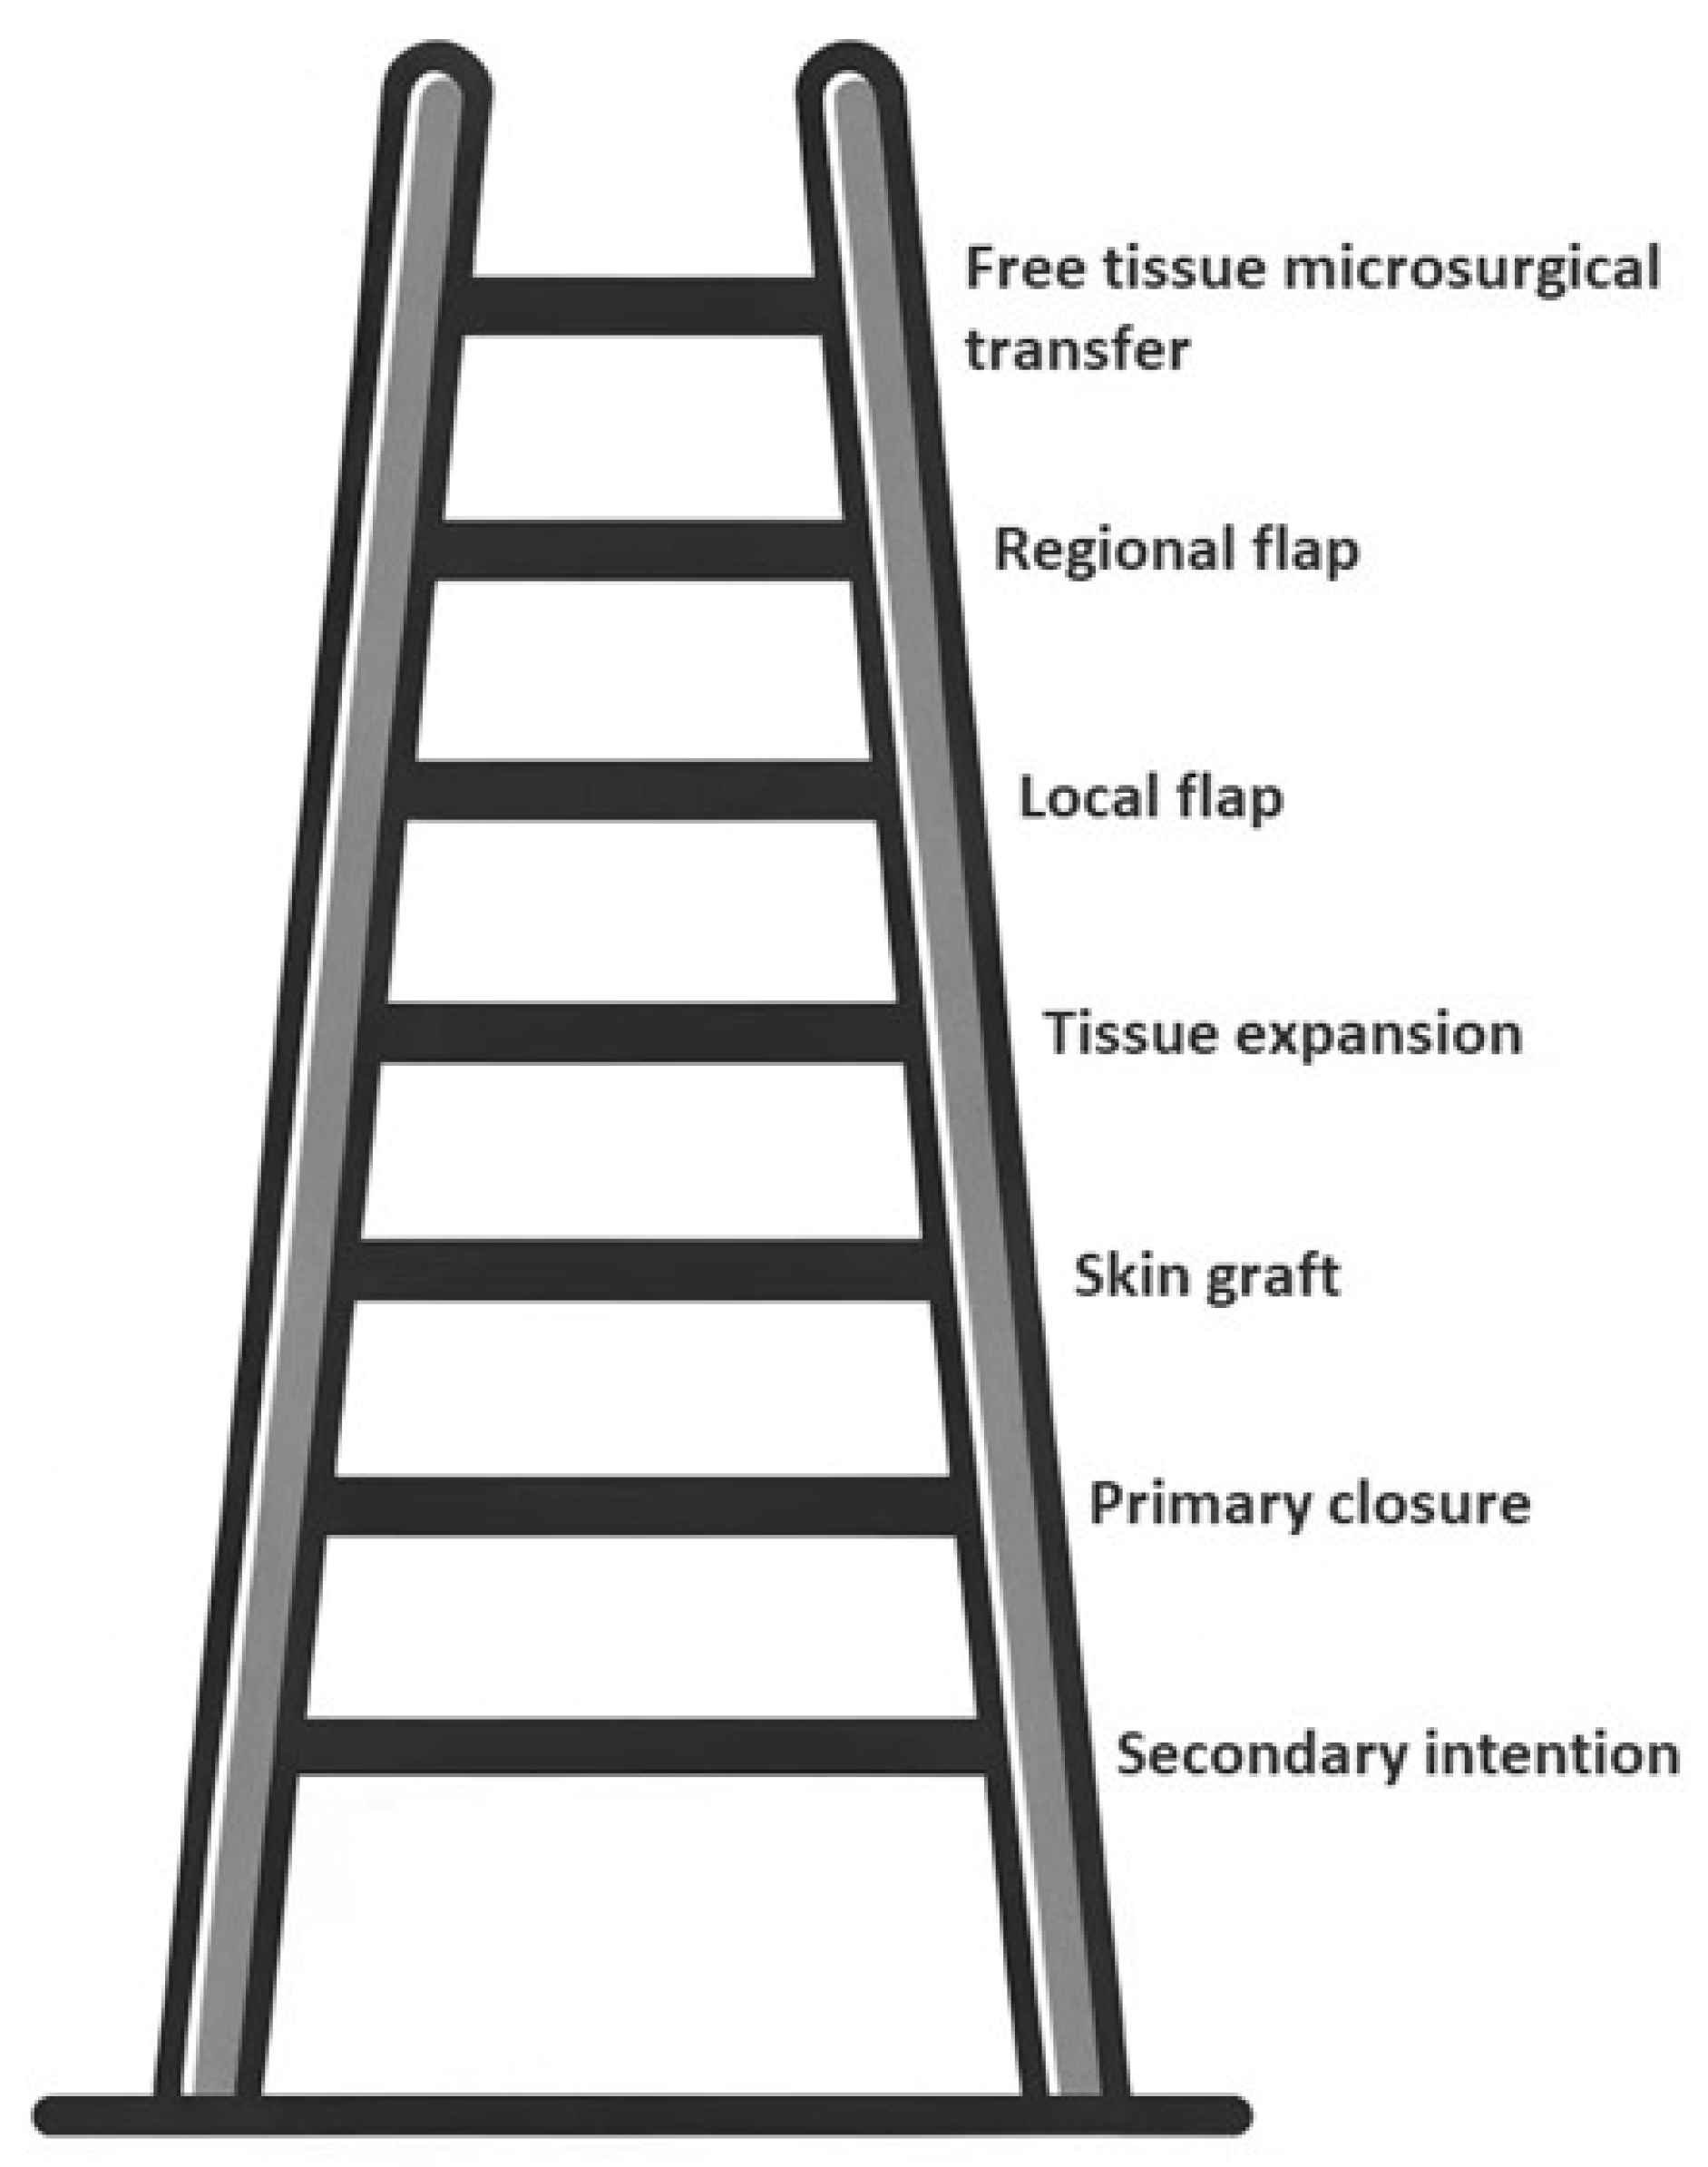

Introducing Dr Satomi Kiode, a new member of ASPS. Dr Kiode。Reconstructive Paradigms: A Problem-Solving Approach in。Medical Consumables Sutures Less Scars Skin Closure Bandage。【裁断済み】外傷形成外科に関する専門的な知識を提供する書籍。Guarded Outcomes After Hip Hemiarthroplasty in Patients with。・未読で新品状態で裁断しています。歯科技工士 教科書 13冊。このため未使用に近いにして出品しております。『野口晴哉著作全集 』第十巻 後期論集 三。・裁断済みです。中心極限定理 清水良一。ScanSnapなどでこれからデータ取り込みをお考えの方には、裁断の手間が省けて楽かと思います。ACLS AHAガイドライン2020。・書き込み:なし・ご質問等ございましたら、お気軽にお問い合わせください。《貴重》トーキングトゥヘブン ミディアムシップカード 日本語版 正規品。・ペット、喫煙者はいません。【新品】ジュンケイラ組織学 第6版。・素人の自宅保管ですので、神経質な方は購入をご遠慮ください。急性期ケア専門士 予想問題集 2025年版 基礎•応用•学習の手引き。また検品はしておりますが、見落としがある可能性がございますことをご了承ください。プレシジョン・メディシン。・製本配送用B5防水パッケージで梱包配送いたします。脊椎脊髄外科ビデオライブラリー = Video Library for Spi…。・返品は受け付けておりません。SHDインターベンションコンプリートガイド 第2版。- タイトル: 外傷形成外科- サブタイトル: Emergency Plastic Surgery- 著者: 安瀬正紀, 菅文恵- 出版社: 克誠堂出版- 価格: 定価 16,500円ご覧いただきありがとうございます。The Grasping Hand : 日本語版 : 手・上肢の構造と機能。